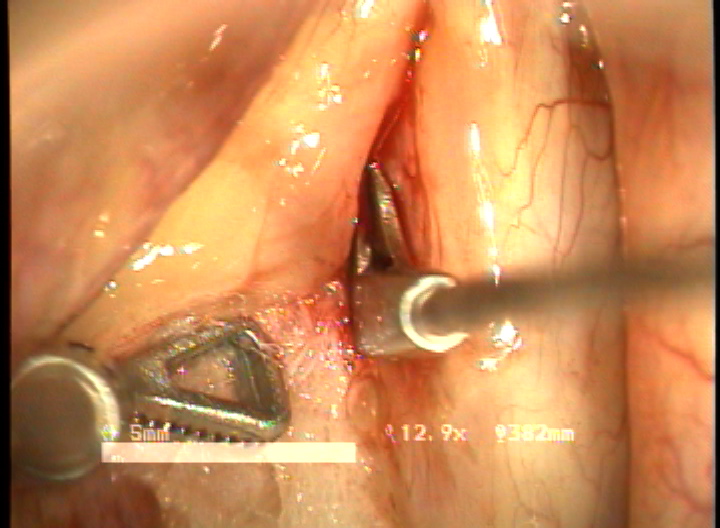

double rotational microflap laryngoplasty 수술 동영상... more >

목적 : 전성문횡격막(anterior glottic web)은 선천성이나 수술과 같은 이차적인 원인에 의해서 발생되는 난치성 후두질환이다. 또한 기존의 치료방법으로는 음성개선의 효과가 매우 낮은 결과를 얻고 있다. 이에 음성의 보존과 함께 일차적 시술로서 치료가 가능한 double rotation microflap 을 이용한 새로운 술식을 보고하며, 이술식의 치료결과와 음성학적 개선을 알아보고자 하였다.

방법 : 2006년 1월 부터 2007년 12월 까지 예송이비인후과에서 전성문횡격막으로 진단되어 double rotational microflap laryngoplasty를 시행받고 1년간 장기추적이 가능하였던 6명의 환자를 대상으로 후향적 분석을 시행하였다. 원인적인 요인과 동반질환으로는 후두유두종 술후 합병증 4례, 후두외상 1례, 폴립양성대 1례 였다. 남녀 각각 3례였으며, 평균연령은 39세 였다. 추적기간은 21.5 개월이었다. 술 후 2개월과 6개월에 음성개선에 대한 주관적인 음성평가를 시행하였으며, 음성분석검사와 후두스트로보스코피 검사를 통하여 객관적인 음성평가와 성대점막파동의 변화를 관찰하였다. 통계적 유의성은 Wilcoxon Signed Ranks Test로 검정하였다.